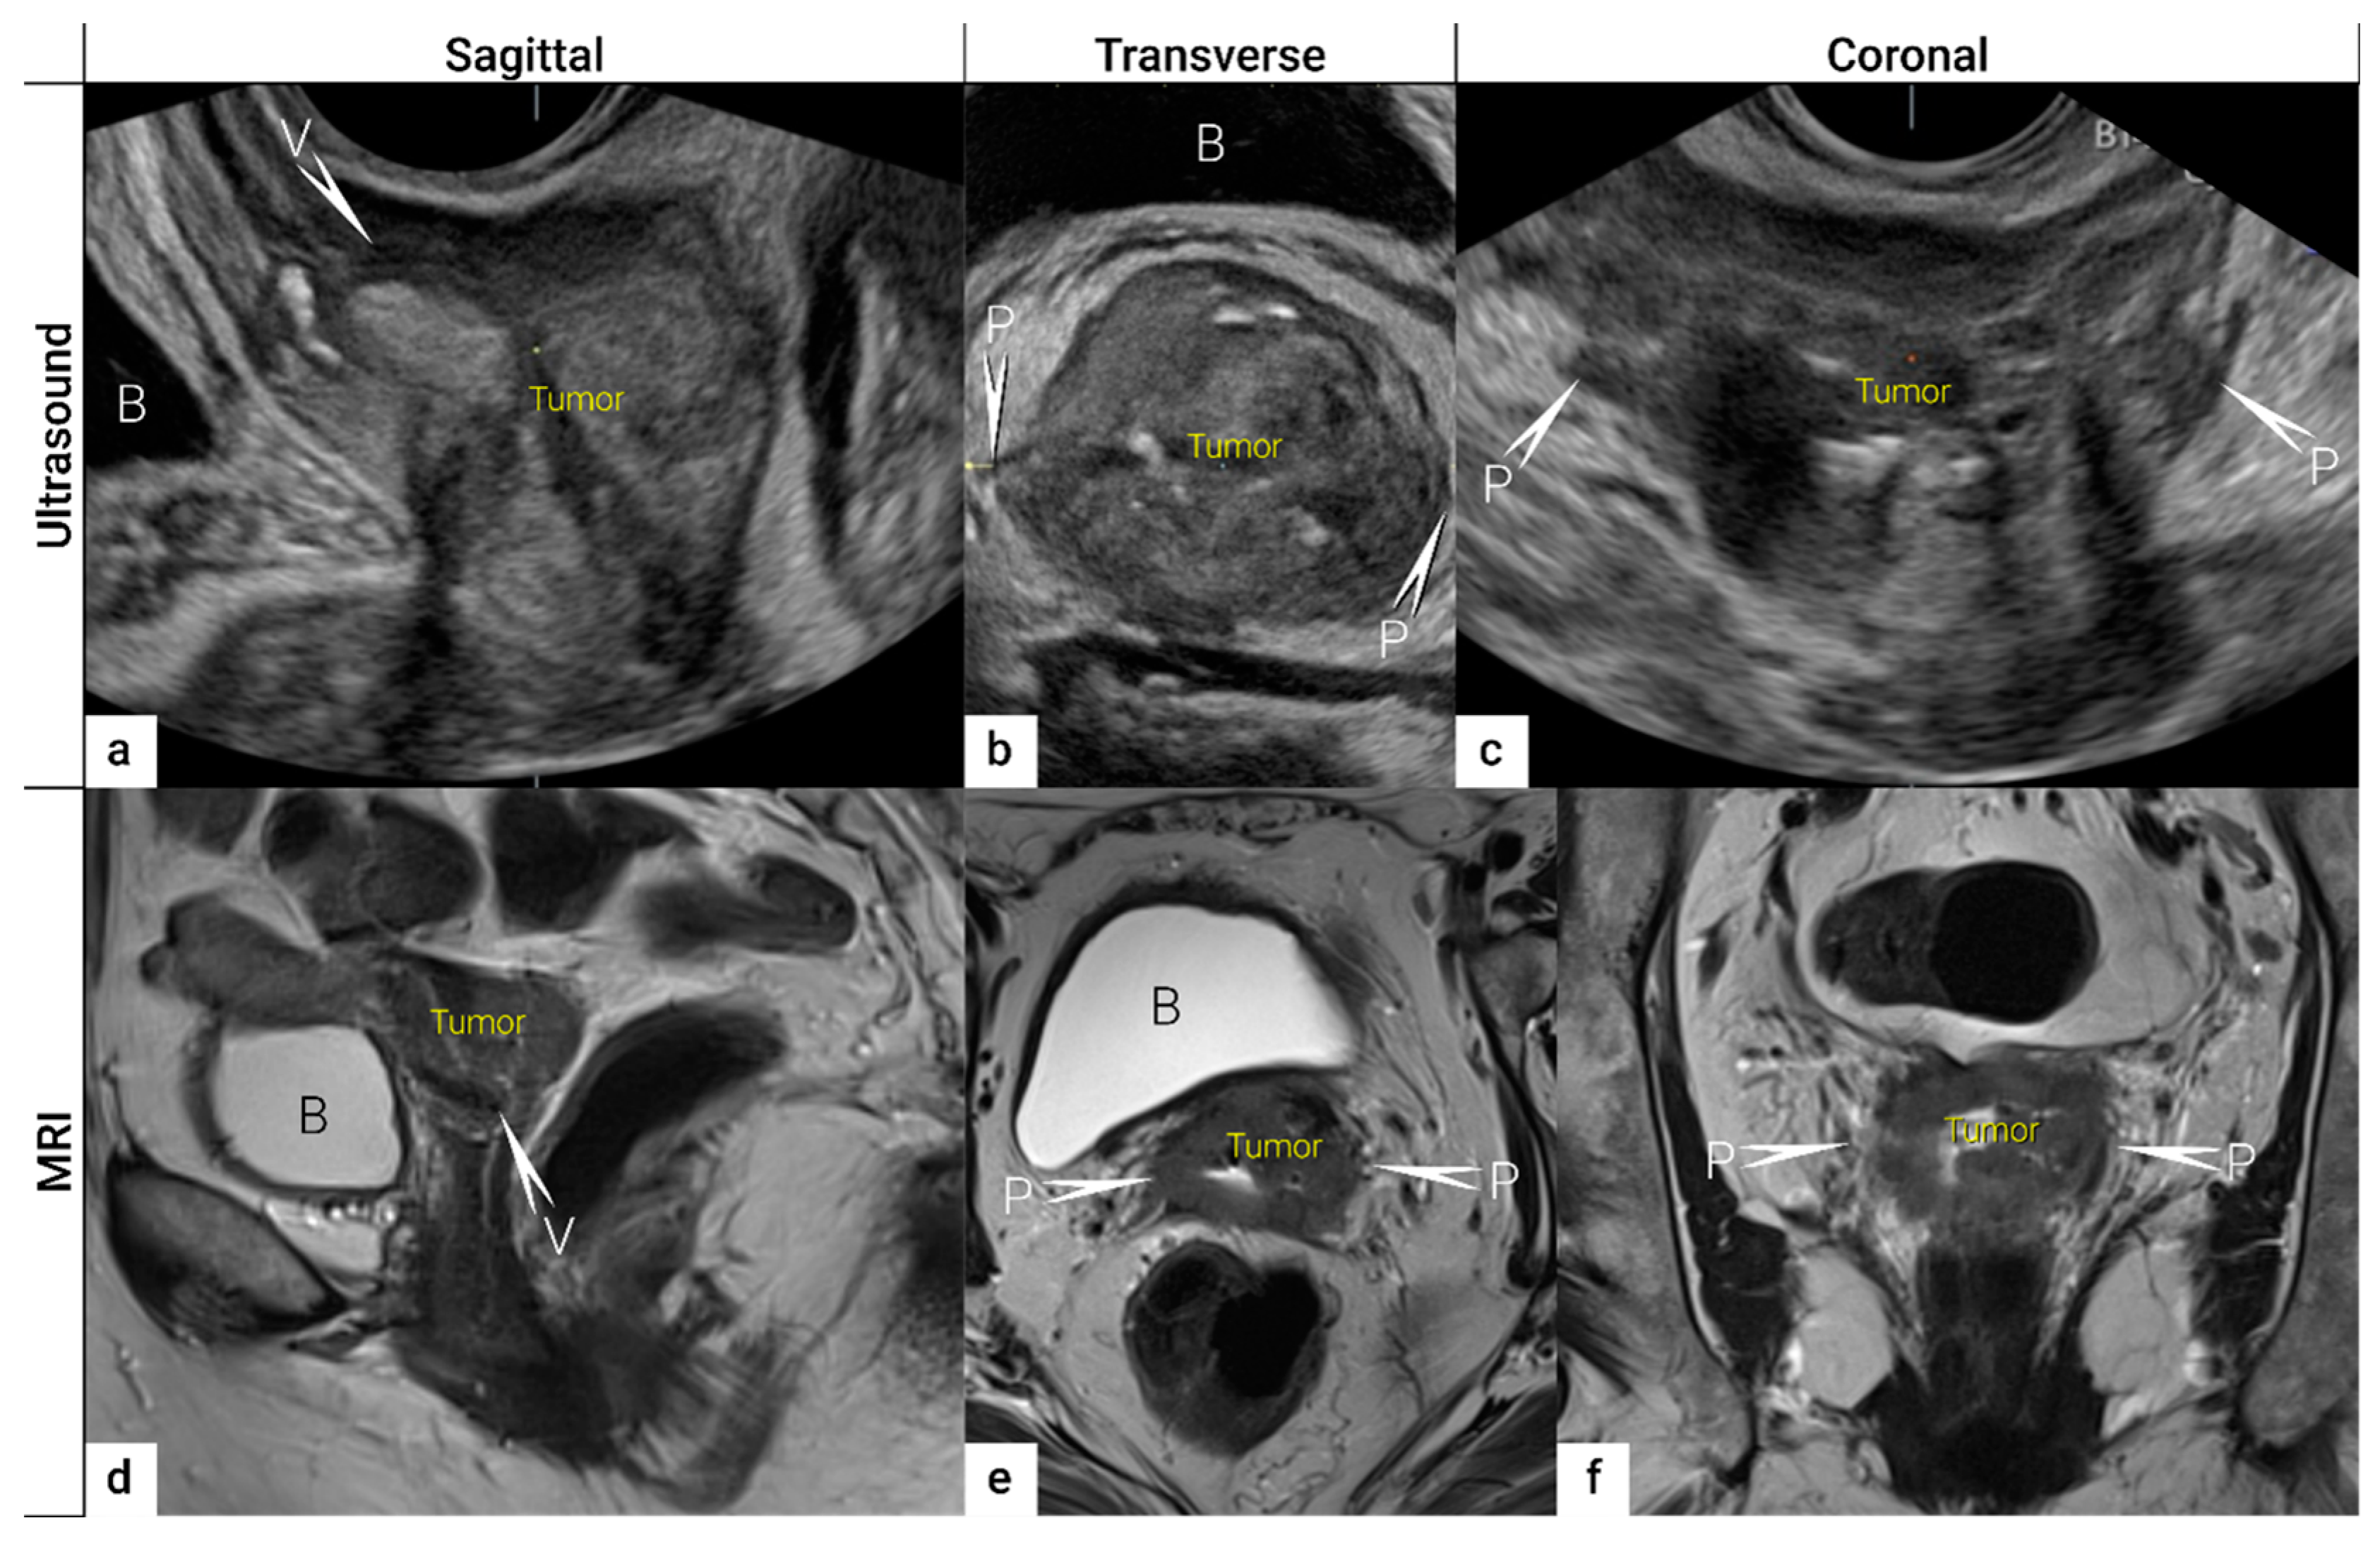

| IB | Carcinoma with deepest stromal invasion >5 mm, limited to the cervix uteri with size measured by maximum tumour diameter. | US: Highly vascularised hypoechogenic (squamous-cell carcinoma) or iso-/hyperechogenic lesion (adenocarcinoma) with intact hyperechogenic pericervical fascia and positive sliding sign between tumour and bladder/rectum. MRI: Tumour has intermediate to high signal on T2W images. Dynamic CE-T1W images depicts tumour as hyperintense in the arterial phase and iso- or hypointense in the venous phase. Tumours characteristically exhibit restricted diffusion on DWI (hyperintensity on high b-value images and low intensity on the ADC maps). Tumour does not disrupt the hypointense peripheral stromal ring (best seen on T2W images). | |

| T2a | IIA | Involvement limited to the upper two-thirds of the vagina without parametrial invasion | US: Highly vascularised tumour infiltrates upper two third of hypoechogenic vaginal wall, maximum diameter of primary tumour is critical to substageT2a1/T2a2. MRI: Involvement of the upper two-third of the vagina is seen as segmental loss of the T2-hypointensity of the vaginal wall. |

| T2b | IIB | Parametrial tumour invasion but no pelvic side wall extension | US: Tumour infiltrates the hyperechogenic pericervical fascia, negative sliding sign, presence of hypoechogenic tumour projections into hyperechogenic parametria. MRI: Tumour disrupts the hypointense peripheral stroma and extends into the parametrium +/− abutting parametrial vessels on T2W images. |